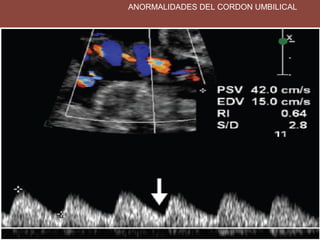

ANORMALIDADES DEL CORDON UMBILICAL

ANORMALIDADES DEL CORDONUMBILICAL (NUDO) PICO SISTOLICO VELOCIDAD DE FIN DE DIASTOLE

• 10.

IR: MENOR DE0.7 S/D MENOR DE 3.5